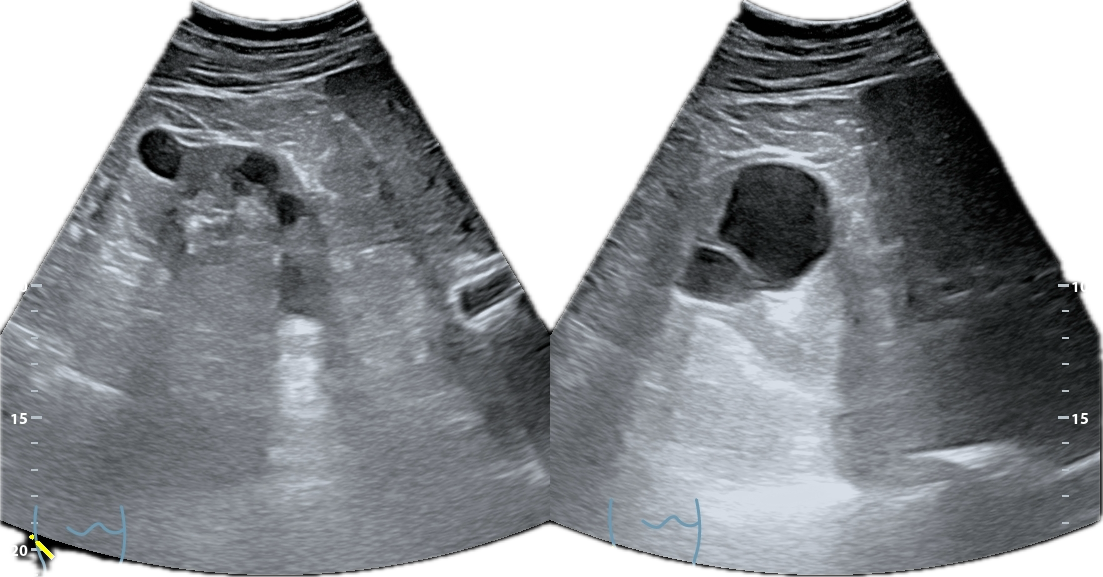

La ecografía abdominal muestra ambos riñones con múltiples quistes corticales y medulares, de diferentes diámetros, distribuidos de forma difusa.

El parénquima presenta un aspecto multiquístico que confiere una morfología global cribo forme, semejante visualmente a un «queso gruyere». No se observan litiasis, ni signos de obstrucción de la vía urinaria.

El quiste de mayor tamaño (aprox. 9 cm) se observa en riñón izquierdo; sin ecos internos, calcificaciones o sextos (categ BosniaK 2). En riñón derecho se aprecian múltiples quistes alguno de ellos con esto grueso en su interior, sin calcificaciones ni componentes sólidos en su interior (categ. BosniaK 2-3).